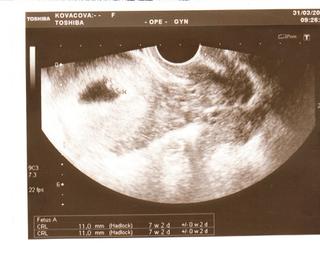

ahojte, Kovik, tak som zvedava ako bude na UTZ, a co ti povie 🙂 . Dali mi vcera aj fotku, a moj muz to dnes naskenoval a poslal strasne vela ludom...som este predsa len chcela pockat, ale on je taky hotovy, ze to hovori ludom na pockanie..no sak hadam mu radost nepokazim. 😉 Petulka: vies co , ja si tiez myslim, ze by tam nieco mohlo byt. Kovik ma pravdu, ze keby tam bolo 0 hcg, tak tam nie je ani len tienik...ja ked som si naivne robila asi po 5 dnoch (v lekarni mi tvrdili, ze to urcite ukaze..no blbost) tak tam nebolo ani stopy, ani po hodine. NO a po par dalsich dnoch sice neukazal v limite, ale po pol hodinke tam uz bola slabsia ciarka. Ja by som ale pockala aspon 12dpo..vtedy mi uz tusim cosi ukazal test. Pre mna vsak celkom dobry ukazovatel bola bazalna teplota, lebo ta sa stale drzala na 37 a neklesala...tak po 10 dnoch som zacala dufat, ze by tam cosi mohlo byt...

tak se hlasím u nas je vše v pořádku srdíčko mame a krásně rosteme . Dostali jsme prukajdu 😀 😀 😀 😀 a jsme 7+2 , ztím, přesně to bude vědět až příště. No v prukajdě mam napsaný 9 tt dle poslední MS, no prý to tam napsat musí, ale pak zvýrazní druhý datum dle UTZ a podle toho se budou řídit